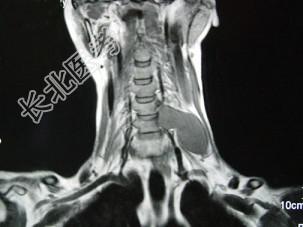

- 单项选择题52岁女性患者,左颈部无痛性包块渐进性增大, MRI检查如图,应需要考虑为 ( )

A、左侧颈部脂肪瘤

B、左侧颈部转移瘤

C、左侧颈部神经纤维瘤

D、左侧颈部神经鞘瘤

E、左侧颈部动脉瘤